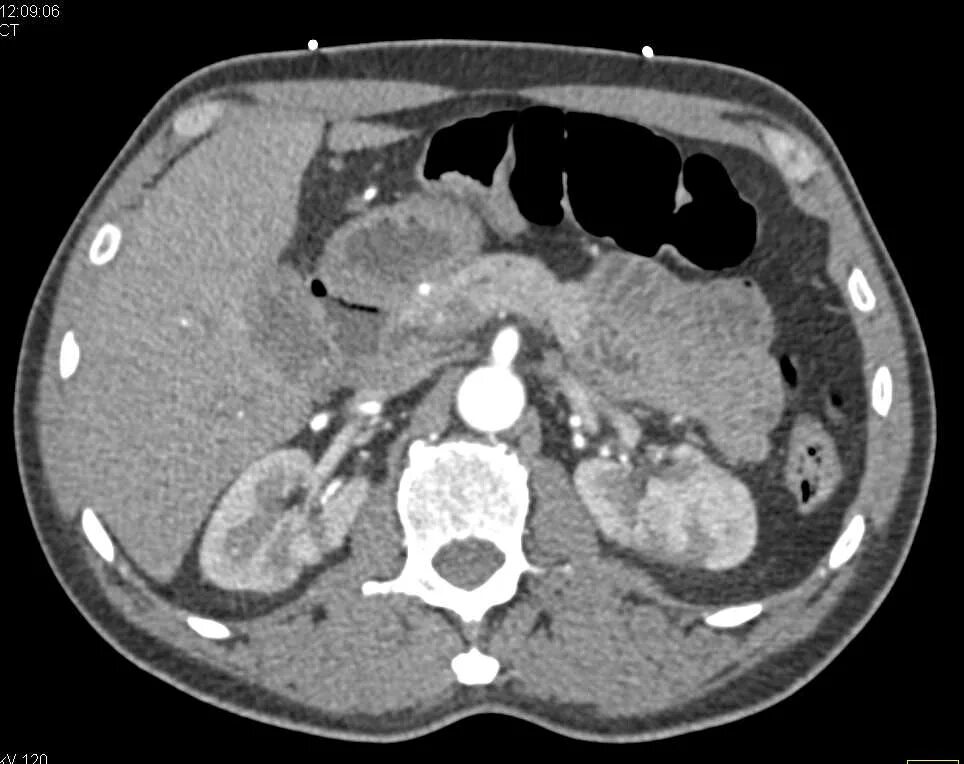

Пиелонефрит кт